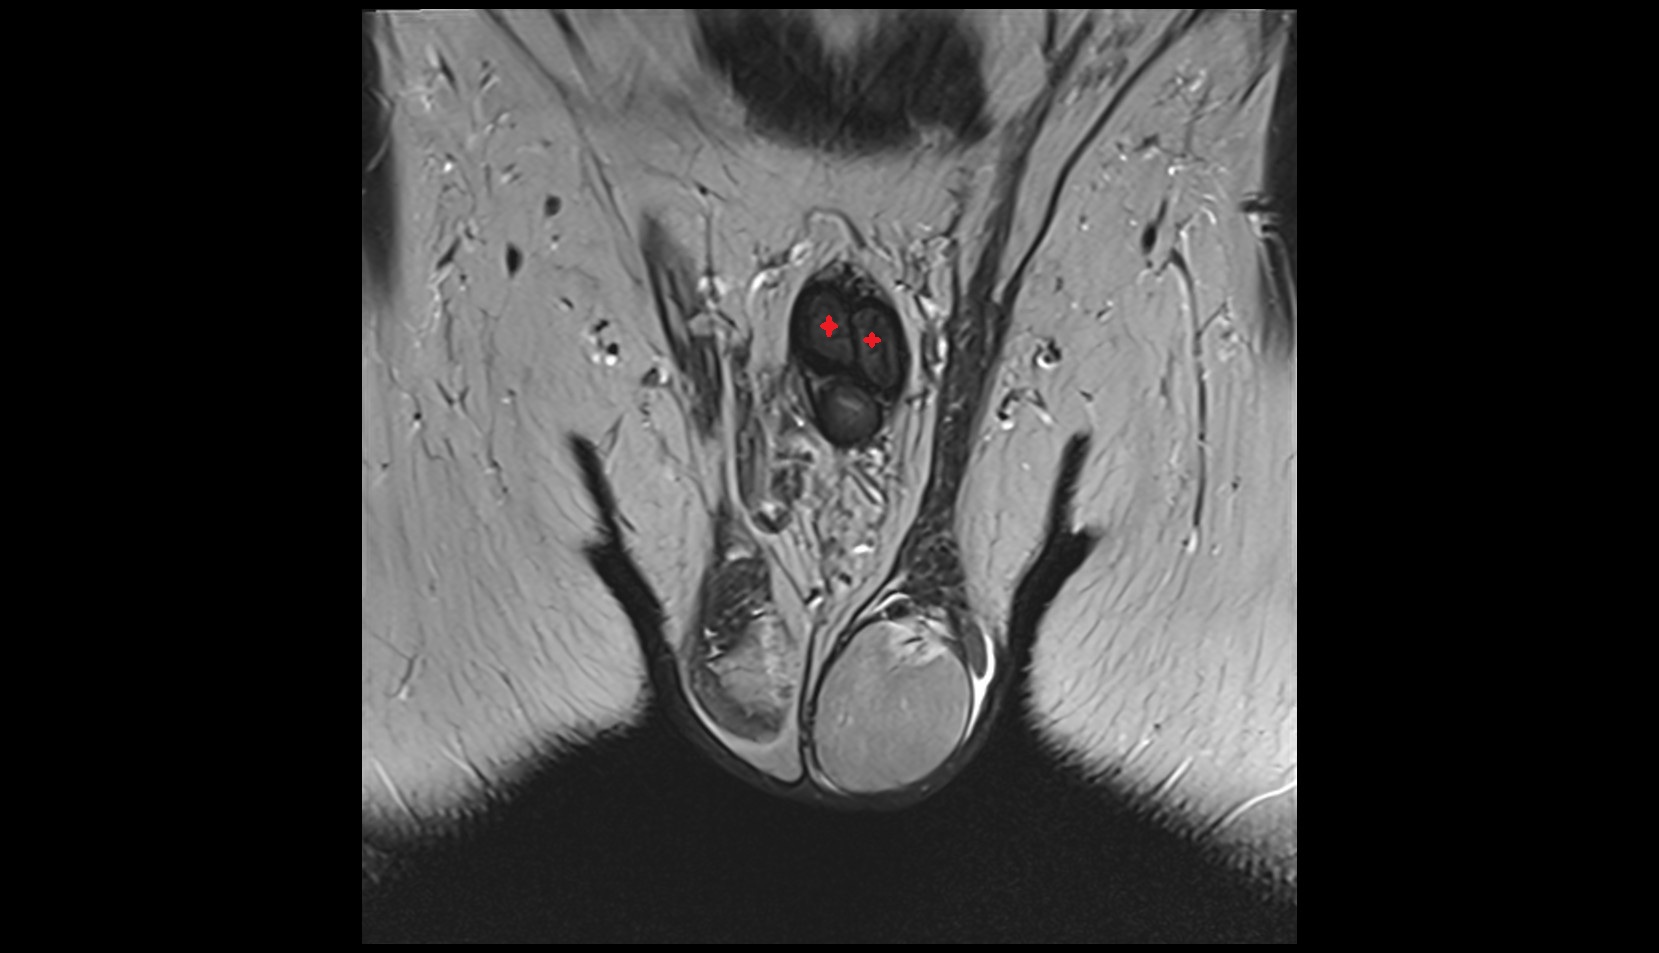

- Corpus cavernosum

- Corpus spongiosum

- Bulb of Penis

- Crus of penis

- Testis

- Tunica albuginea (penis)

- Tunica albuginea of testis